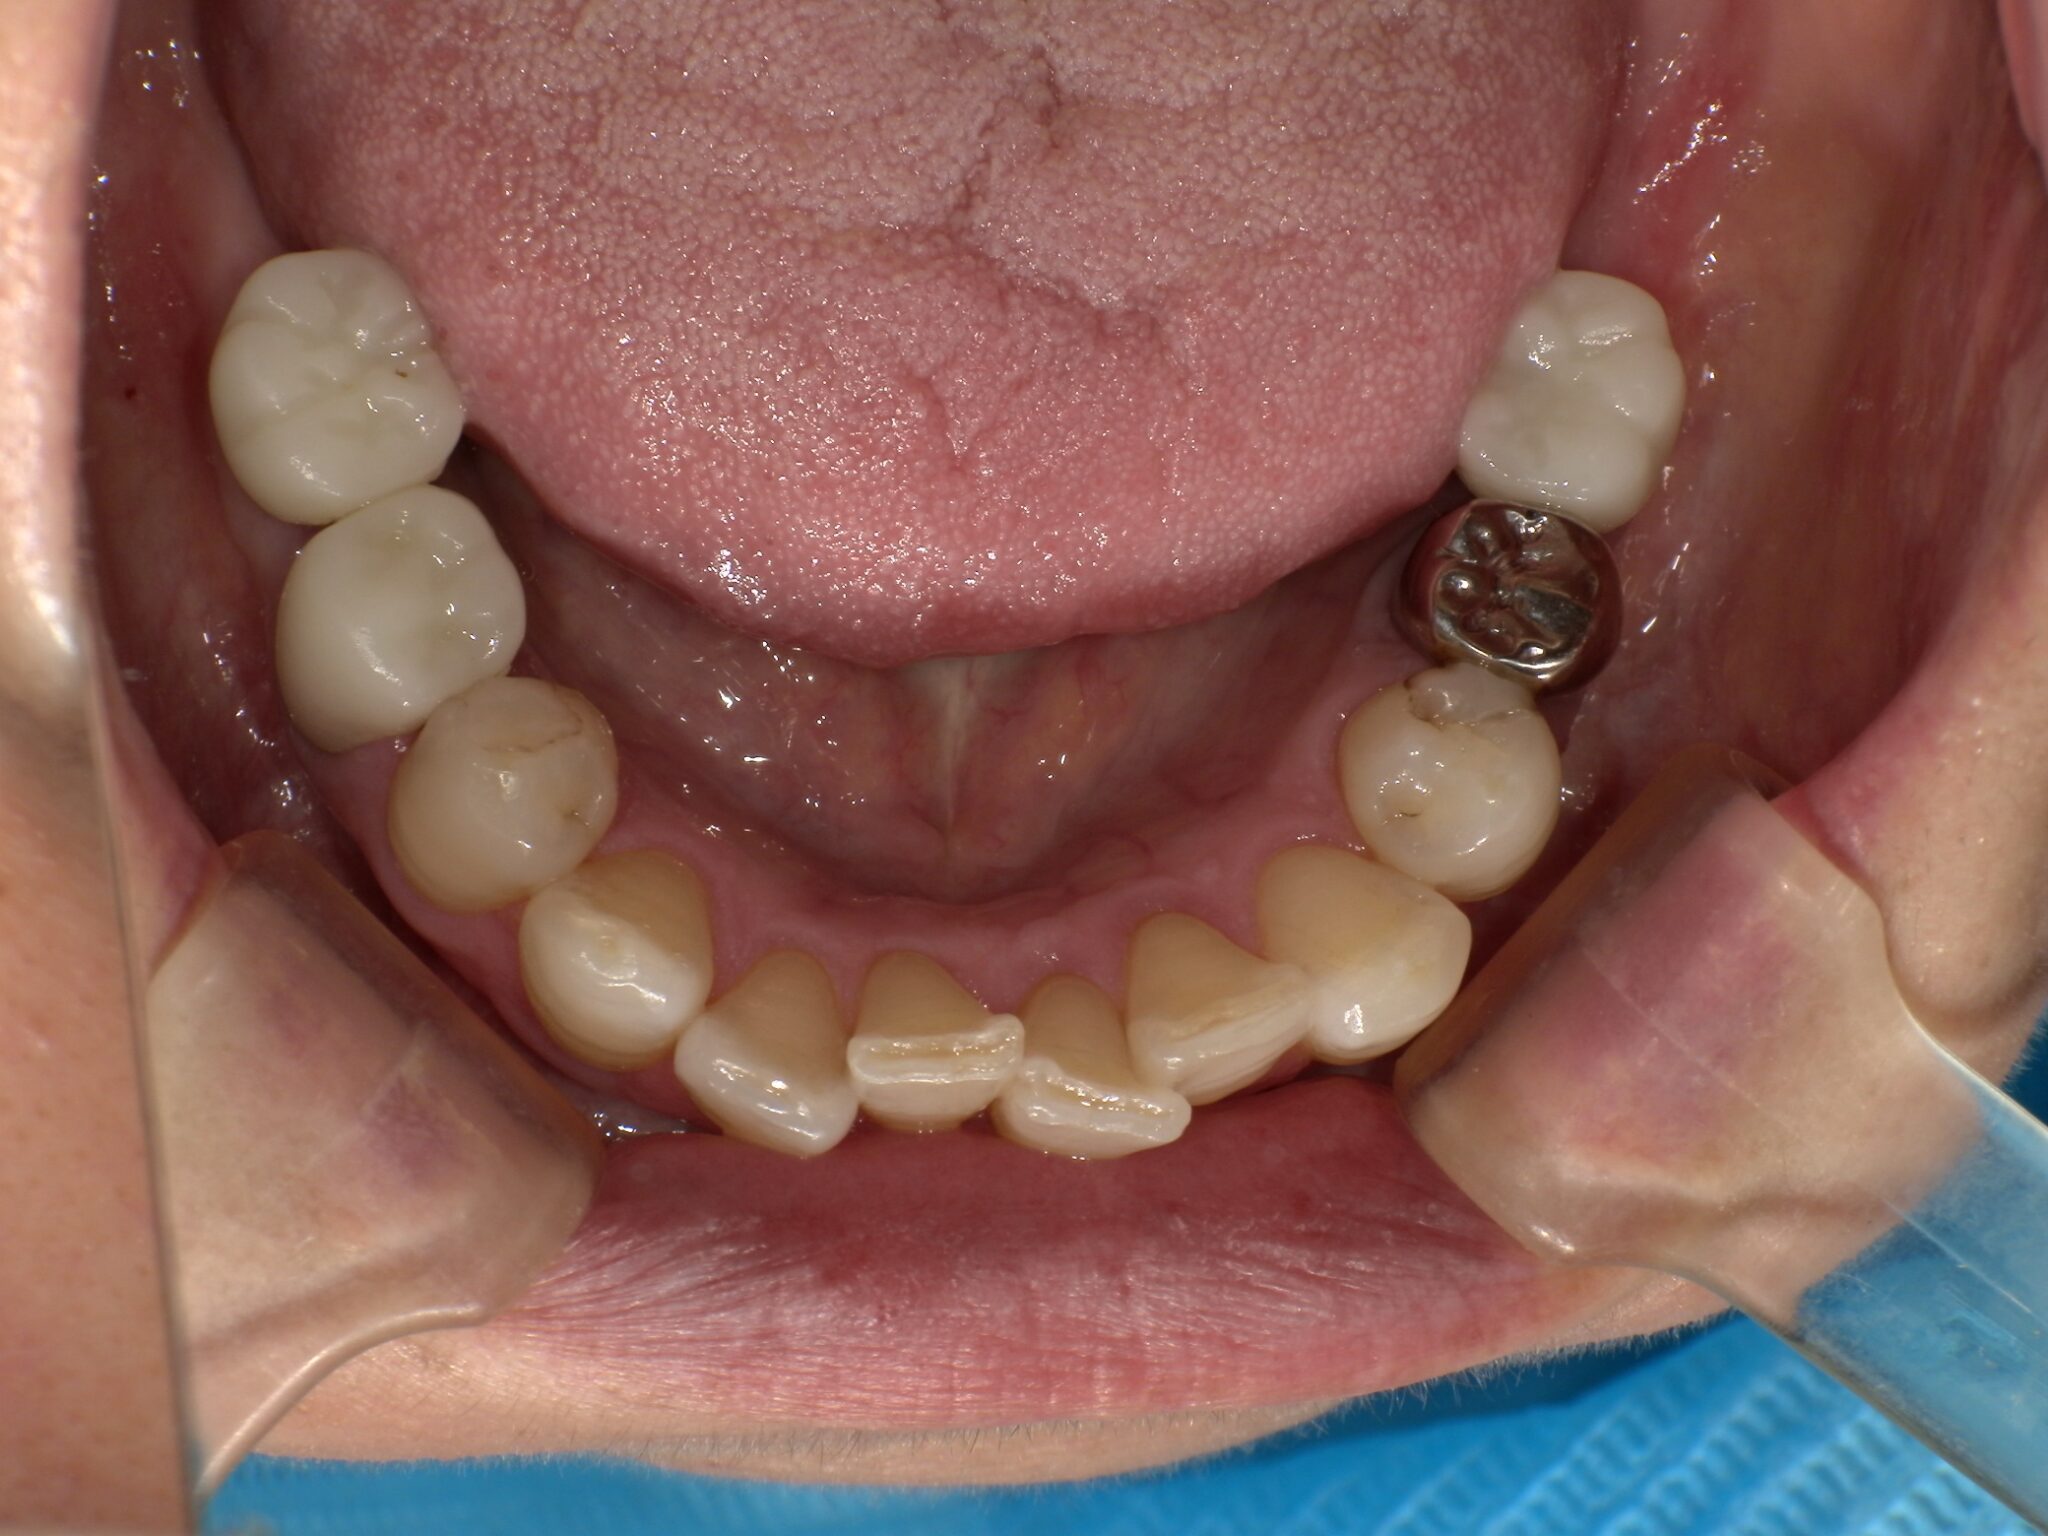

全顎治療症例

| 主訴 | 全体的に見た目を綺麗にしたい。奥歯でしっかり噛みたい。 |

| 診断名・ 主な症状 |

臼歯部欠損 |

| 年齢 | 70歳 |

| 治療内容 | インプラント埋入(右上4・6,左上4・6,右下6,左下6) ジルコニアBr(右上3―左上3) ジルコニア(右下5,左下5) |